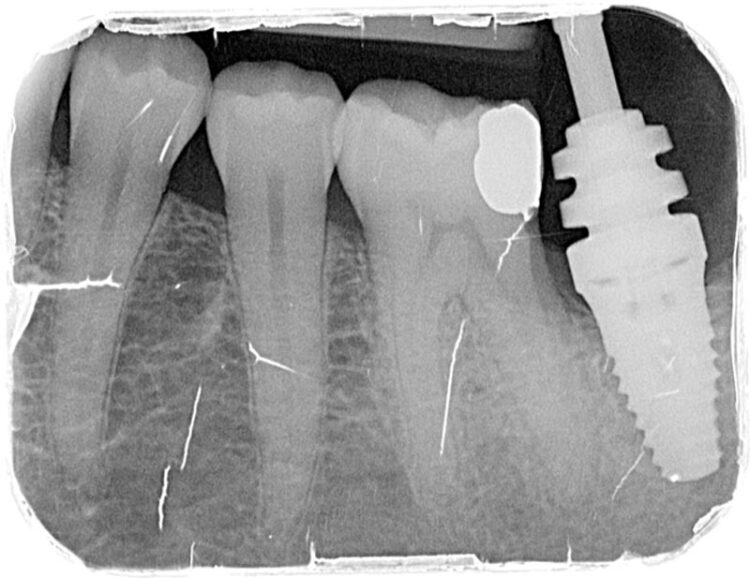

3-D radiographic examination showed sufficient bone available for the placement of a 5.8mm x 9mm BioHorizons Camlog tapered tissue level implant. Surgical placement of this implant involved a two-sided flap and there was no need for hard or soft tissue augmentation. The implant was placed with excellent primary stability and therefore a single-staged approach was followed with a healing abutment being placed at implant placement.

The implant was then left to heal and integrate for three months. No temporary prosthesis was required during this phase.

After three months the healing abutment was then removed. The presence of the healing abutment facilitated the development of an emergence profile from the implant platform during the healing phase. A fixture level impression was taken and a screw-retained crown with the screw emerging in the mid-occlusal area was fabricated. The crown was made on a zirconia framework on a hybrid base abutment layered with e.max ceramic with ultra-polished zirconia subgingivally.